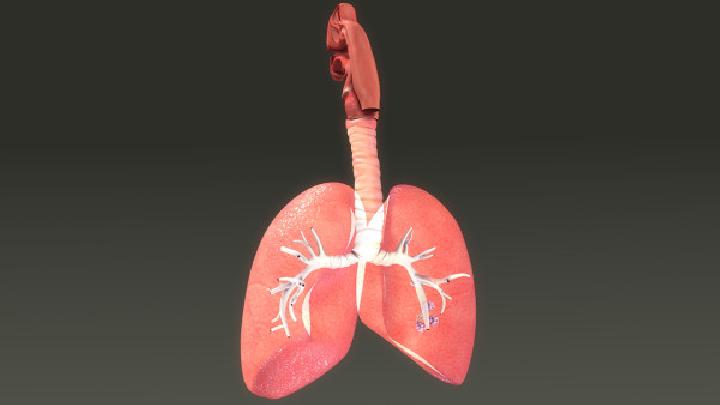

医院数字区 - 内科 - 呼吸内科 - 肺结核 - 危害

结核病的易感者主要为小儿,肺结核的传染源主要是成人患者,尤其是家庭内传染极为重要,接触活动性肺结核病人的小儿的结核病感染率、发病率与患病率都较一般小儿显著为高。 肺结核都有哪些危害呢?肺结核危害介绍如下: 1、重症感染多见 患肺结核排菌的母亲,若用力咳嗽或打喷嚏,可造成啼哭的婴儿吸入肺内大量结核菌。因婴儿对结核感染无特异免疫力,可引起重症感染,表现出发病急、进展快、预后差。 患儿组织和器官对结核菌高敏性,肺内可表现为原发病灶的周围炎,肺外表现除结核菌素试验强阳性外,还可表现为多发性浆膜炎、一过性多发性关节炎、疱疹性角膜结膜炎和结节性红斑。 3、淋巴系统广泛波及 在肺原发病灶形成过程中,结核菌可沿淋巴管抵达肺门和纵隔淋巴系统,尤其颈部淋巴结肿大最多见。肿大淋巴结还可产生压迫症状,内部干酪样坏死,甚至穿破支气管,产生支气管播散,并成为慢性结核中毒症和结核复燃的根源。 4、全身播散倾向

关于肺结核的信息 当我们患上肺结核的时候,一定要注意了,因为不止是疾病本身存在着危害,此病还具有传染性,所以我们一定要特别注意,那么怎样避免肺结核的传染呢,带着这个疑问我们咨询了相关专家,专家为我们介绍了如下内容。  肺结核算是一种危害较大的疾病了,并且专家说此病的发病率逐渐上升,所以我们必须多多的进行了解,此病严重时患者可能会出现浑身乏力,不思饮食的症状,是比较难受的,那么肺结核要怎么护理呢,那么下面我们就来了解一下吧。  肺结核早期治疗费用是多少?任何的疾病都是早点治疗效果更好,其实肺结核当然也不例外,但是对于治疗这个疾病到底多少钱很多人都不知道,那么,今天我们一起了解下肺结核早期治疗费用是多少吧!  要想拥有一个健康的身体,平时就要多多注意一些常发疾病,而肺结核就是其中的一种,专家称肺结核就是指结核菌所引起的肺部慢性疾病,目前治疗肺结核的治疗方式是以化学治疗方式为主,原则一般是早期发现,早期治疗为主,那么肺结核能不能治好呢。  很多人都不清楚自己为什么会发生肺结核这种病,专家说因为此病的传染方式有很多,所以很有可能是被传染了,那么肺结核是通过什么传染的呢,下面就来为大家详细的介绍一下,希望下面的内容能够对大家有所帮助。  肺结核根据发病进程进行划分,可分为进展期、好转期以及稳定期,不同分期症状表现不同。  相信大家都知道肺结核这种疾病,此病在生活当中还是十分多见的,如果有人患上此病的话,我们要接受一定的疾病检查工作,那么肺结核该做什么检查呢,今天专家为我们总结肺结核的检查知识点,希望可以帮助到肺结核的患者。  肺结核根据症状与具体病因划分,可分为:原发型肺结核、继发型肺结核、血行播散型肺结核、结核性胸膜炎、菌阴肺结核五种分型。  说到肺结核,大家一定都不陌生,最起码都听说过这种疾病,那么去哪个医院治肺结核好呢,这是很多患者在治疗前都想知道的问题,因为选择一家好的医院才能帮助患者治疗疾病,给患者提供最大的帮助,那么治疗肺结核最好的医院在哪里呢,接下来就跟小编一起去看看吧。  专家说现在患上肺结核的人不断增加,但是我们对于此病的认识还是很少,所以在发生此病之后,不能及时的进行治疗,专家提醒,一旦出现了肺结核的类似症状,一定要及时去检查,下面我们来了解一下肺结核的检查有哪些。  如果发现你的身边,有一些朋友经常性的咳嗽,或者是出现咯血的现象,就要注意了,这很有可能是肺结核的症状,肺结核给患者带来很多的痛苦,生活中可以引发该病出现的病因有很多,我们需要了解清楚,一起来看看患上肺结核有哪些原因。 |